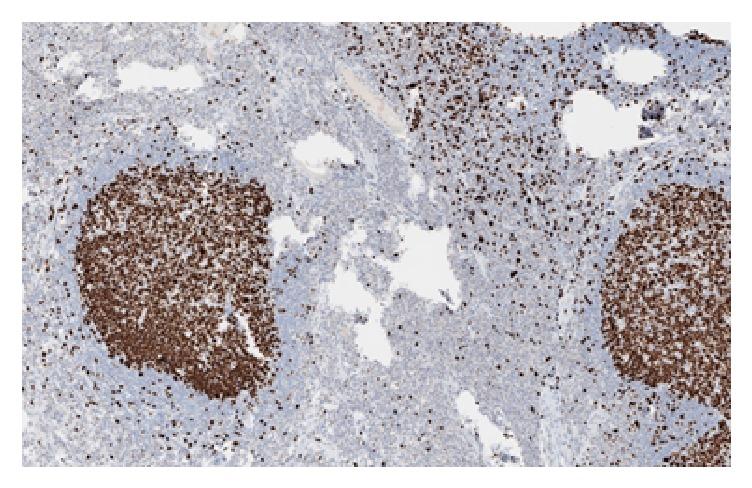

Benign lymphoid polyps are uncommon lesions of the small bowel and the colon to a lesser degree that are mostly found in children. There are only few reported cases in adults in which the lesions were predominantly polypoid and described as lymphonodular hyperplasia. We present a case of a large benign lymphoid polyp in the transverse colon of a 64-year-old lady who was referred to our care for a history of alteration in her bowel habit and anemia. Colonoscopy showed a 3 cm (Paris 1p) friable polyp which was excised and retrieved. Histopathology examination confirmed its benign nature supported by immunohistochemical studies. Benign lymphoid polyp is a rare condition posing a diagnostic challenge as it can be misinterpreted as a malignant lesion.